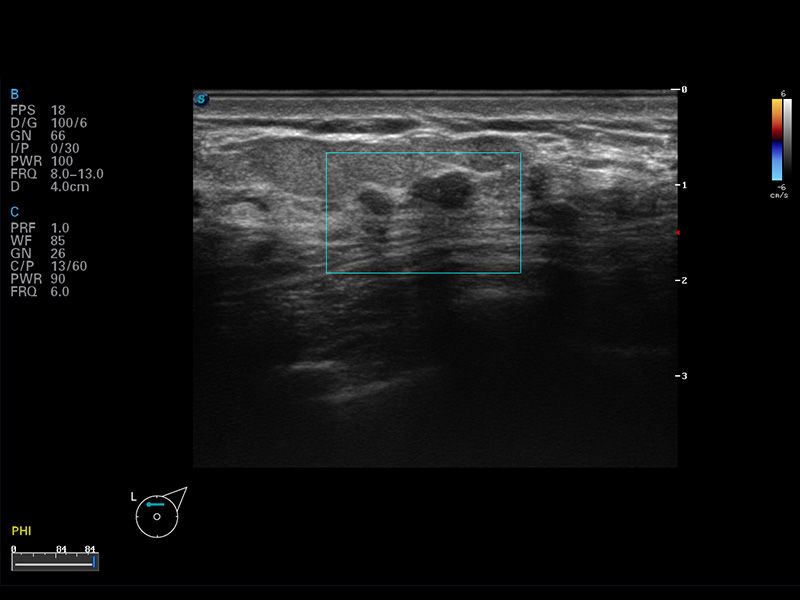

S8 EXP便携式彩色多普勒超声诊断仪是亚星官网研发的高端全身应用型便携彩超。高通道的VIS平台融合可视化(Visual)、智能化(Intelligent)和人性化(Smart)的特点,配以亚星官网自主研发生产的探头大家族,使您能够快速、准确的获得病人信息,提高工作效率的同时减轻疲劳。

成像技术

多波束形成器

μ-Scan微米成像

谐波成像

空间复合成像